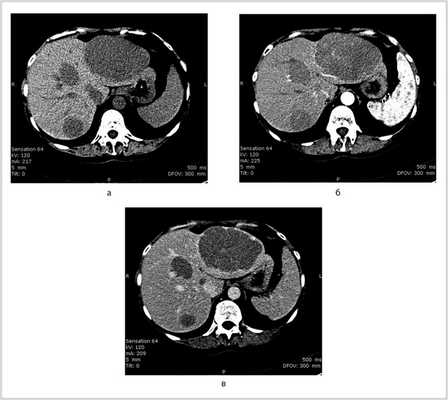

Пациентка N., 1959 года рождения, с 1984 г. наблюдалась в НИИ ревматологии с диагнозом БШ. В течение многих лет принимала глюкокортикостероиды, цитостатики (хлорбутин, циклофосфан), получала курсы пульс-терапии метилпреднизолоном. В декабре 2010 г. госпитализирована в городскую клиническую больницу с жалобами на боли в правом верхнем отделе живота. При обследовании выявлены множественные очаговые образования в печени, которые были расценены как поражение печени солидной опухолью (гепатоцеллюлярная карцинома (?), метастазы из первично невыявленного очага (?). В марте 2011 г. обратилась в НИИ ревматологии с жалобами на резко выраженные боли в правом подреберье, слабость, профузную ночную потливость. При обследовании правая доля печени выступала на 4 см ниже края реберной дуги, резко болезненна при пальпации. Периферические лимфатические узлы и селезенка не увеличены. При ультразвуковом исследовании (УЗИ) органов брюшной полости выявлены множественные гипоэхогенные узлы в обеих долях печени с максимальным размером 110×105 мм в левой доле и 95×94 мм в правой доле. По результатам мультиспиральной компьютерной томографии (МСКТ) с внутривенным контрастированием органов грудной полости, брюшной полости и малого таза визуализированы множественные очаговые образования низкой плотности с однородной структурой и достаточно четкими контурами в обеих долях печени (рис. 1). Других патологических изменений в исследуемых областях не обнаружено. Общий анализ крови без особенностей. В биохимическом анализе отмечалось повышение активности аспартатаминотрансферазы 135 ед/л (норма

Рис. 1. Данные МСКТ. а — до контрастирования: множественные очаги низкой плотности с однородной структурой и достаточно четкими контурами в обеих долях печени; б — артериальная фаза контрастирования: определяется слабое и неоднородное накопление контраста в очагах; в — выделительная фаза: отмечается накопление контраста по периферии очагов. В структуре наибольшего образования стали дифференцироваться множественные тяжи.